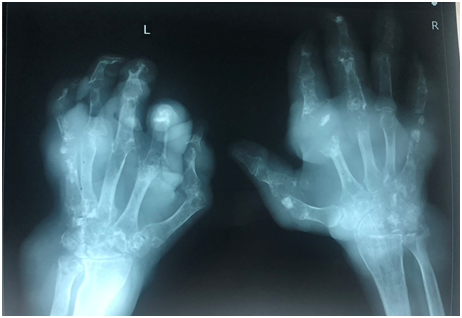

Fig 2: Images of chronic tophaceous gout minicking RA

Fig 3: Images of disabling chronic tophaceous gout

- X ray of the affected joint – cortical break in bone suggestive of gout (overhanging edge with sclerotic margin), can be normal in acute gout

Fig 4: Images of an x ray on hands of severe chronic tophaceous gout